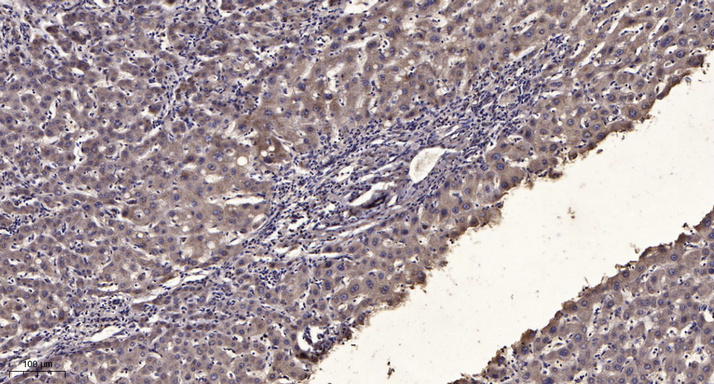

WB, IHC, IF, IP

Optimal working dilutions should be determined experimentally by the investigator; Suggested starting dilutions are as follows:IHC 1:50-300; IF 1:200.

α-tubulin Monoclonal Antibody(8F11) AbFluor™ 680 Conjugated specially designed for your Immunofluorescence analysis.

α-tubulin Monoclonal Antibody(8F11) AbFluor™ 680 Conjugated specially designed for your Immunofluorescence analysis.